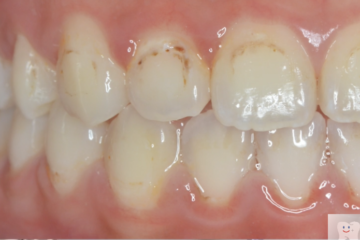

脱灰の深さ

ワイヤー治療の方が3倍深く脱灰が進んでしまう

-

脱灰の面積

マウスピース治療の方が2倍広がる

ワイヤー矯正後

マウスピース矯正後